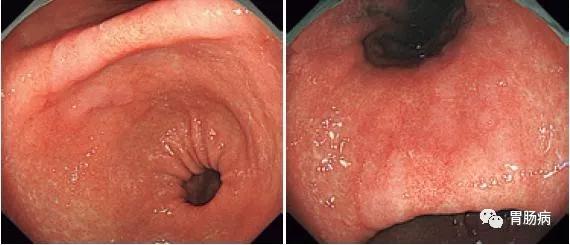

洛阳东大肛肠医院 的想法: 这是胃镜下:正常胃黏膜和慢性萎缩性胃炎